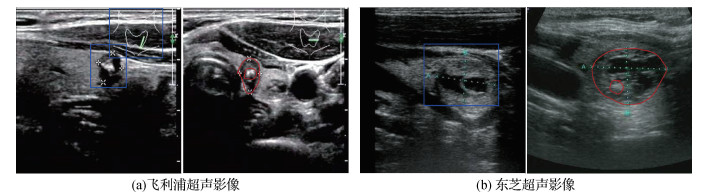

• 甲状腺超声影像的元优化多级对抗域适应网络

应翔, 刘振, 朱佳琳, 姜汉, 张瑞璇, 高洁

2023, 28(1): 234-247. DOI: 10.11834/jig.220454

甲状腺超声影像的元优化多级对抗域适应网络

摘要:目的计算机辅助诊断是临床诊断中一种重要的辅助手段。然而在多机型超声影像的应用现状中,单一深度卷积神经网络面临难以从不同数据源中提取样本特征的问题,导致模型在区分多源数据方面性能欠佳。为提升单一深度模型在多源数据的泛化能力,本文提出一种无监督域自适应网络。方法将深度对抗域适应方法应用于多源甲状腺超声影像分类任务,通过生成对抗思想提取源域图像与目标域图像的域不变特征,提出一种多级对抗域自适应网络(multi-level adversarial domain adaptation network,MADAN)。将元优化(meta-optimized)策略引入对抗域适应的学习中,将域对齐目标和样本分类目标以协调的方式联合优化,提升了模型对无标记目标域数据的分类性能。结果在包含4种域的甲状腺超声影像数据集上实验,与7种经典域自适应方法比较。实验结果表明,MADAN在全部迁移任务中取得90.141%的目标域样本平均分类准确率,优于残差分类网络和多种经典域自适应分类网络。融合元优化训练策略后的MADAN在目标域的测试平均准确率提升约1.67%。结论本文提出的元优化多级对抗域适应网络一方面通过多级对抗学习进行图像域不变特征的提取,另一方面使用元优化方式改进模型训练过程的优化策略,将带有人工标记的源域信息有效迁移至目标域,提升了单一模型对于不同域数据的泛化性能。

关键词:计算机辅助诊断(CAD);多机型甲状腺超声影像;域自适应;元优化;生成对抗网络(GAN)